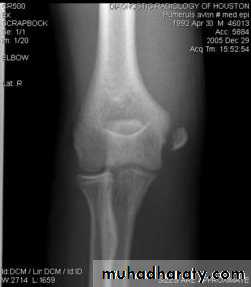

Fracture medial epicondyle of the humerus

It is occur due to fall on out stretched hands ; the medial epicondyl is avulsed by the effect of the strong flexor muscles of the wrist . If the elbow joint is dislocated or subluxated even momentarily , the fracture piece may introducedinto the joint

Clinically :

History of trauma , pain and tenderness , swelling , sensation and power of the fingers should be tested to exclude ulnar nerve d

amage

Minor displacement less than 5 mm. need only back slab in elbow flexed , after 7 days do full p.o.p. for 2-3 weeks .If the piece is trapped into the joint , then it must be freed either by manipulation under anesthesia , if failed or the piece is severely displaced then we should do open reduction and fixation by K wire or screw .

Complication : early : ulnar nerve damage .